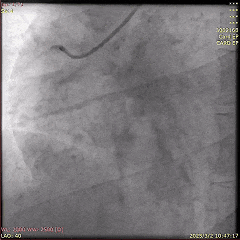

5天后,为患者进行第二次PCI,旨在处理LCx病变。冠脉造影显示,LCx中段模糊病变部位闭塞,术中于病变处植入药物洗脱支架,成功实现血管再通。

第二次PCI中的冠脉造影